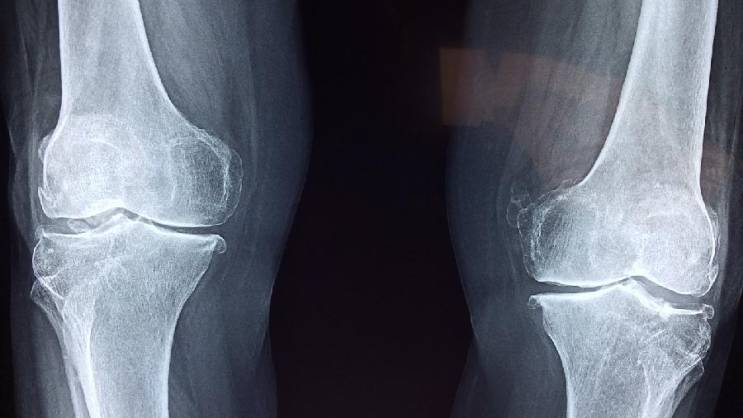

Kosti često oslabe i postanu lomljive bez ikakvih simptoma, a toga postajemo svesni tek kada dođe do preloma.

„Pošto je slabljenje kostiju često neotkriveno, prvi način na koji ljudi mogu da saznaju koliko su im kosti zdrave je skeniranje gustine kostiju, ili DEKSA skeniranje, koje se preporučuje za svaku ženu stariju od 65 godina, mlađe žene u riziku od razvoja osteoporoze i muškarce starije od 70 godina“, rekao je za „The Parade“ dr Heter L. Hoflih.

„Nažalost, osteoporoza i osteopenija su često tiha stanja. Većina ljudi ne oseća ništa u svojim kostima dok ne dođe do preloma“, upozorila je ona.

Međutim, prema riječima dr Fišman, postoji rani znak da kosti slabe, a to je skupljanje.

„Dok neki ljudi vjeruju da je smanjenje obima zgloba znak slabljenja kostiju, to je zapravo manje tačan znak od gubitka visine“, primetila je ona.